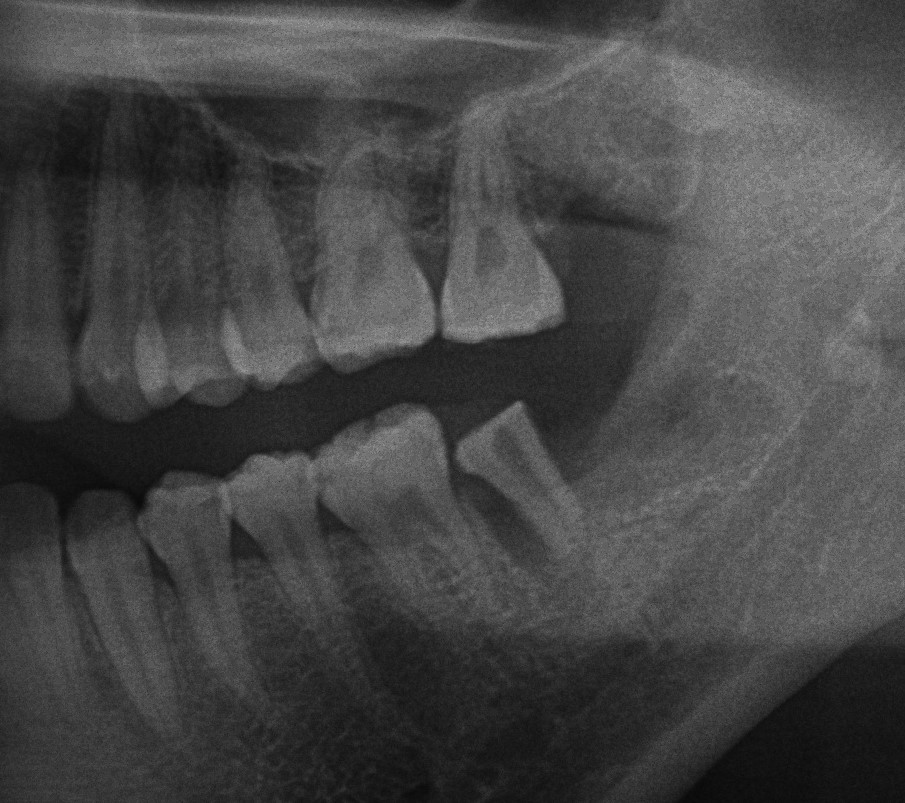

歯牙移植術の術後のレントゲン写真です。